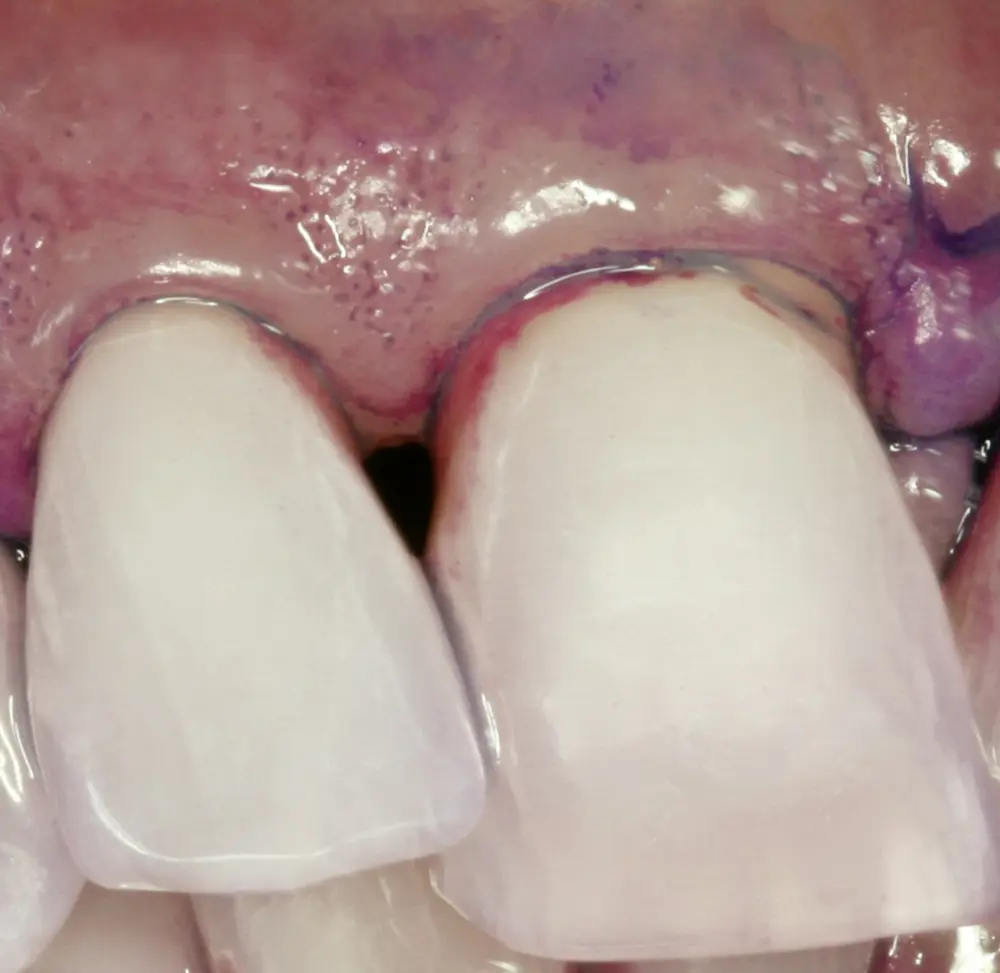

Einige der Mundbakterien haben die Fähigkeit, sich an die Zahnoberflächen anzuheften und sich dort zu vermehren. So entstehen im Laufe der Zeit bakterielle Zahnbeläge (Biofilm), die sich besonders am Zahnfleischrand ausbreiten (s. Abb. 2). Deshalb hat der Körper eine Abwehr entwickelt, die ein Eindringen von Bakterien zwischen Zahnoberfläche und Zahnfleischsaum in das Körperinnere mit Bindegewebe und Knochen verhindert, denn: Im Körperinneren verursachen Bakterien erhebliche Probleme.

Dieser Abwehrmechanismus macht sich als Entzündung des Zahnfleischsaums (Gingivitis) bemerkbar. Werden die bakteriellen Zahnbeläge entfernt, klingt diese Gingivitis nach wenigen Tagen ab. In der Auseinandersetzung von bakteriellem Reiz und der Abwehrlage des Körpers kommt es bei wenigen Menschen früher oder bei den meisten später zu Entgleisungen dieser Infektabwehr.

Eine erfolgreiche Behandlung der parodontalen Entzündung kann nicht nur die lokalen Symptome der Erkrankung des Zahnhalteapparats und damit Zahnverlust vermindern (s. Abb. 3 u. 4), sondern auch die Stoffwechseleinstellung verbessern. Die Reduktion des HbA1c-Werts lag bei Typ-2-Diabetikern drei Monate nach einer nichtchirurgischen Parodontitisbehandlung zwischen 0,4 und 0,5 Prozent, was durchaus nennenswert ist.